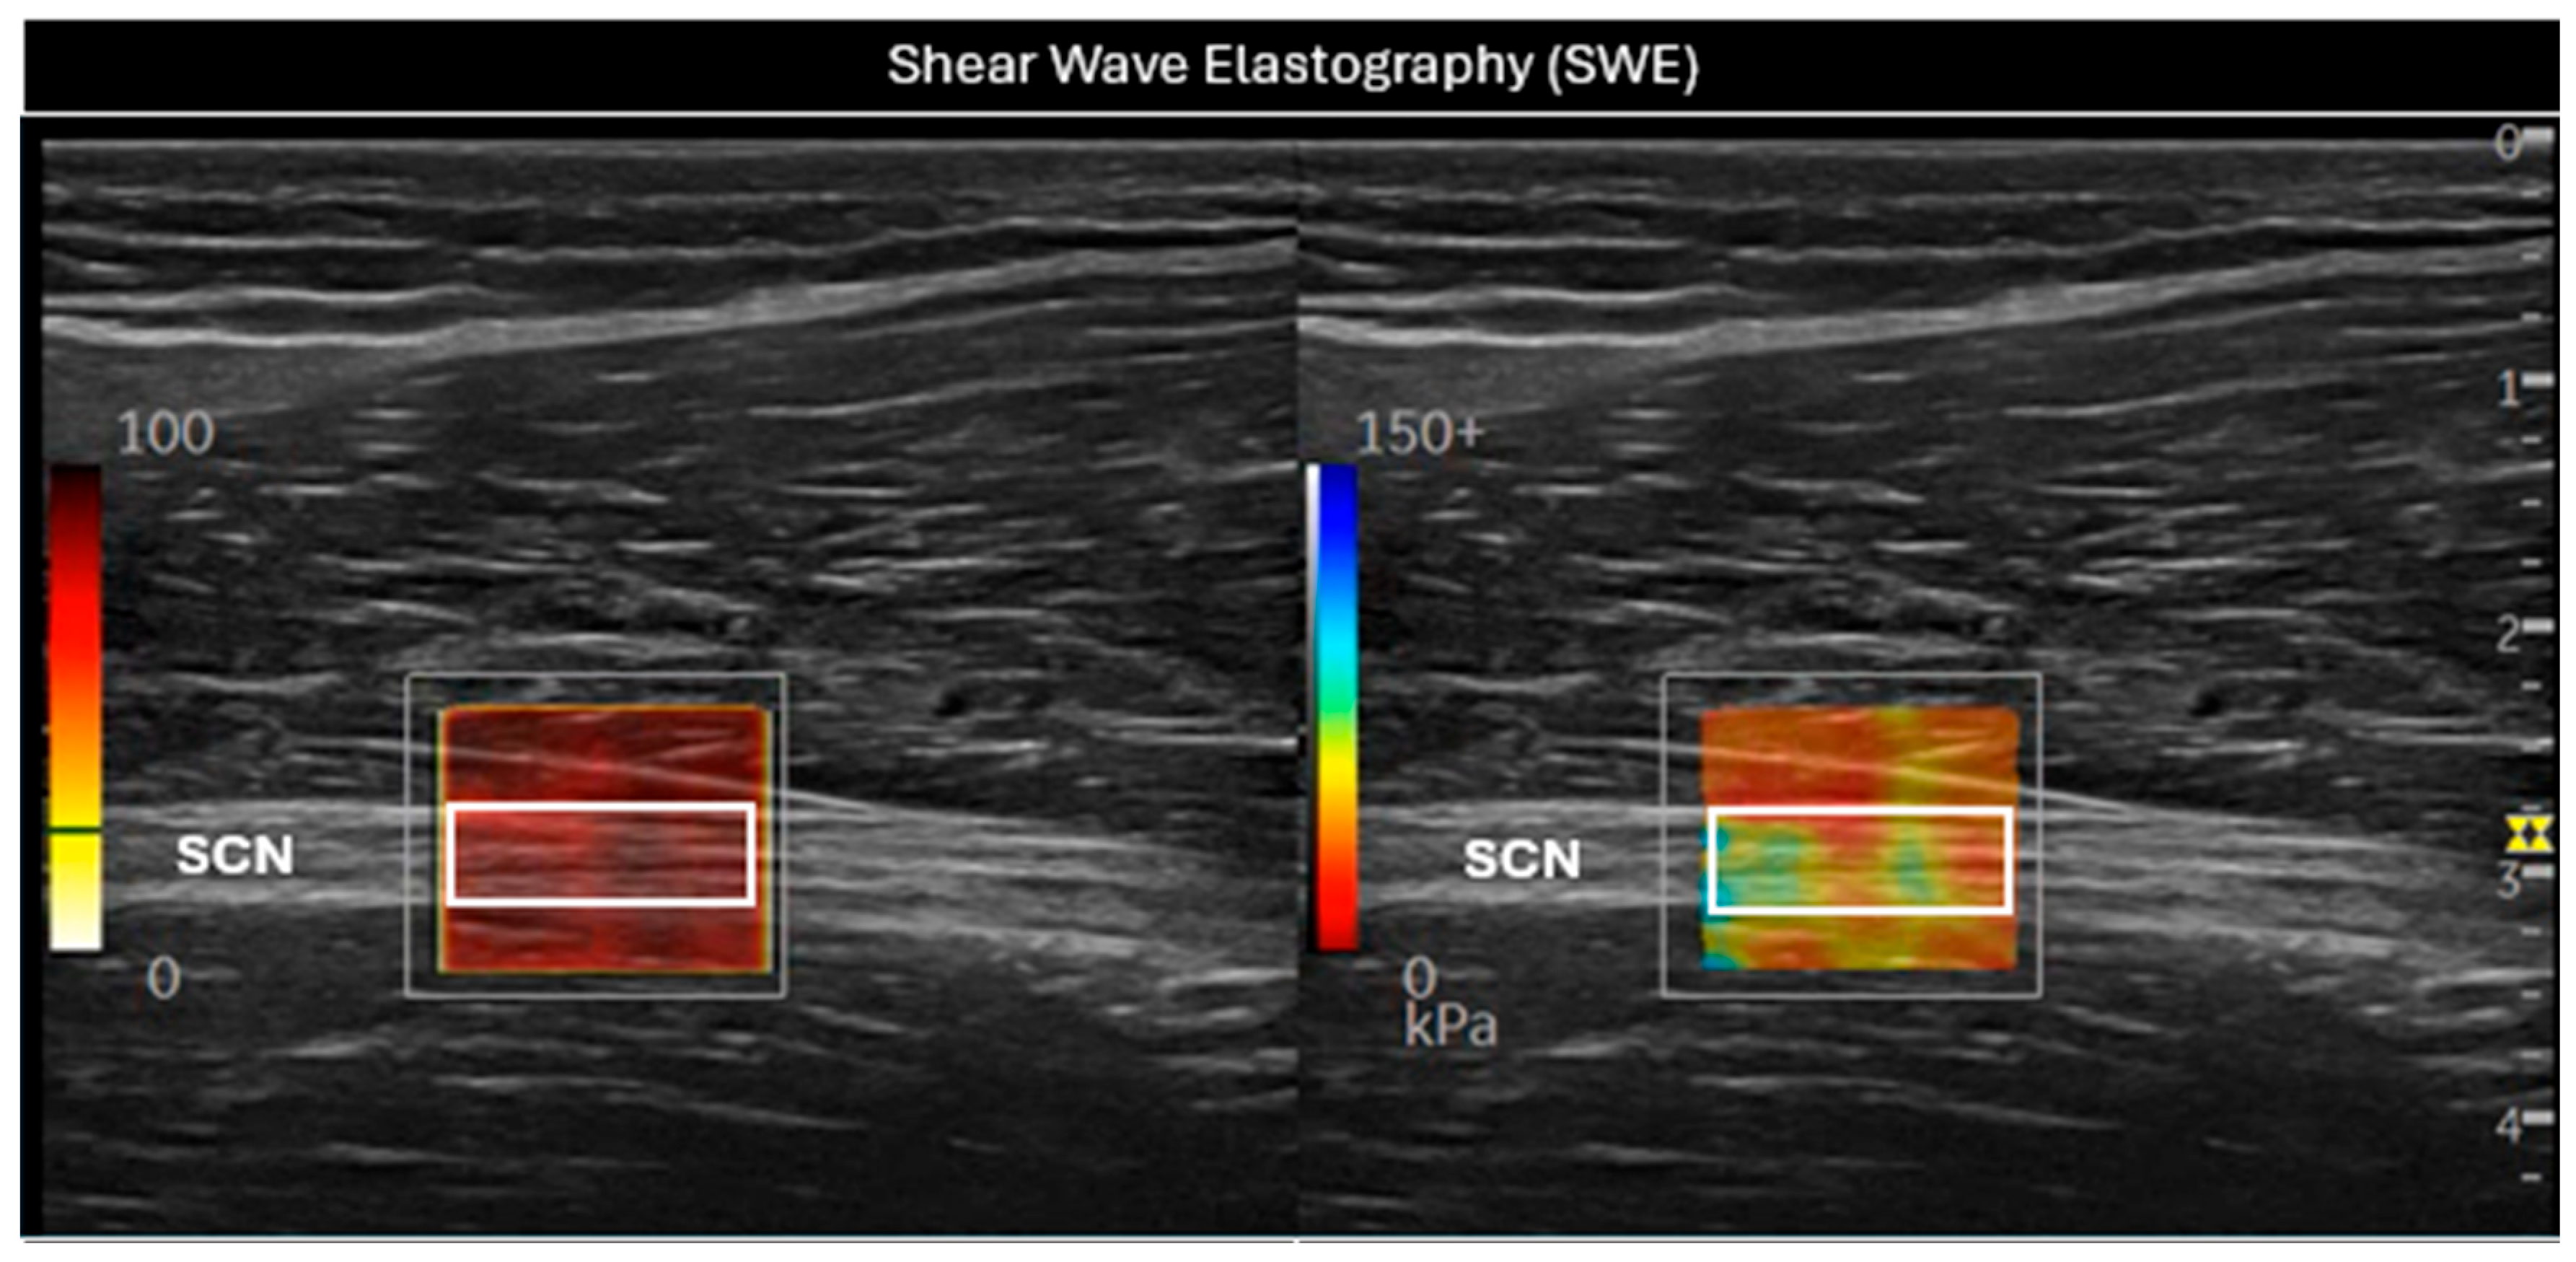

In this position, SWE was initiated (Figure 2), using the default preset with a frequency range of 100–500 Hz, a singular value decomposition (SVD) of 3.2 points, and a gain setting of 75 dBs. The SWE system enabled the selection of a 2 mm2 (white rectangular Q-box 1 mm × 2 mm, Figure 2) region of interest (ROI) within the elastography window, providing average values for the Young Modulus (kPa) and shear wave speed (SWS, m/s). The size of the Q-box was kept constant for all subjects in order to standardize the measurements. The final measurement was determined as the average of three consecutive images to assess intra-class reliability [26,27].

Figure 2. Evaluation of the sciatic nerve (SCN) in the long axis using shear wave elastography (SWE). In the (left) image, a white rectangular Q-box can be seen within the SWE P9R3 elastography system window, used to measure the SWS. In the (right) image, the stiffness of the nerve was assessed through the white rectangular Q-box. SCN = sciatic nerve.